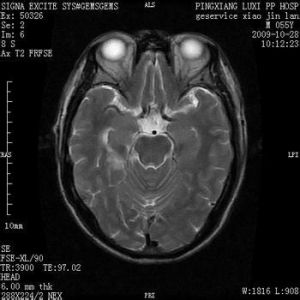

腦缺血灶就是腦部毛細血管發生堵塞後形成血管中空,血液不再流過,局部腦細胞缺氧壞死後形成的病灶.一般症狀是出現頭暈頭痛等現象,如果是病情發展後就有可能導致偏癱、語言不清、大小便失禁、失去記憶力、甚至是意識糊塗、失明等情況。

腦缺血

腦的短暫性血液供應不足並出現症狀就叫做短暫性腦缺血發作,是一種常見的急性腦血管病。病人突然發病,類似腦出血或腦梗塞的表現,一般在24小時內完全恢復正常,...